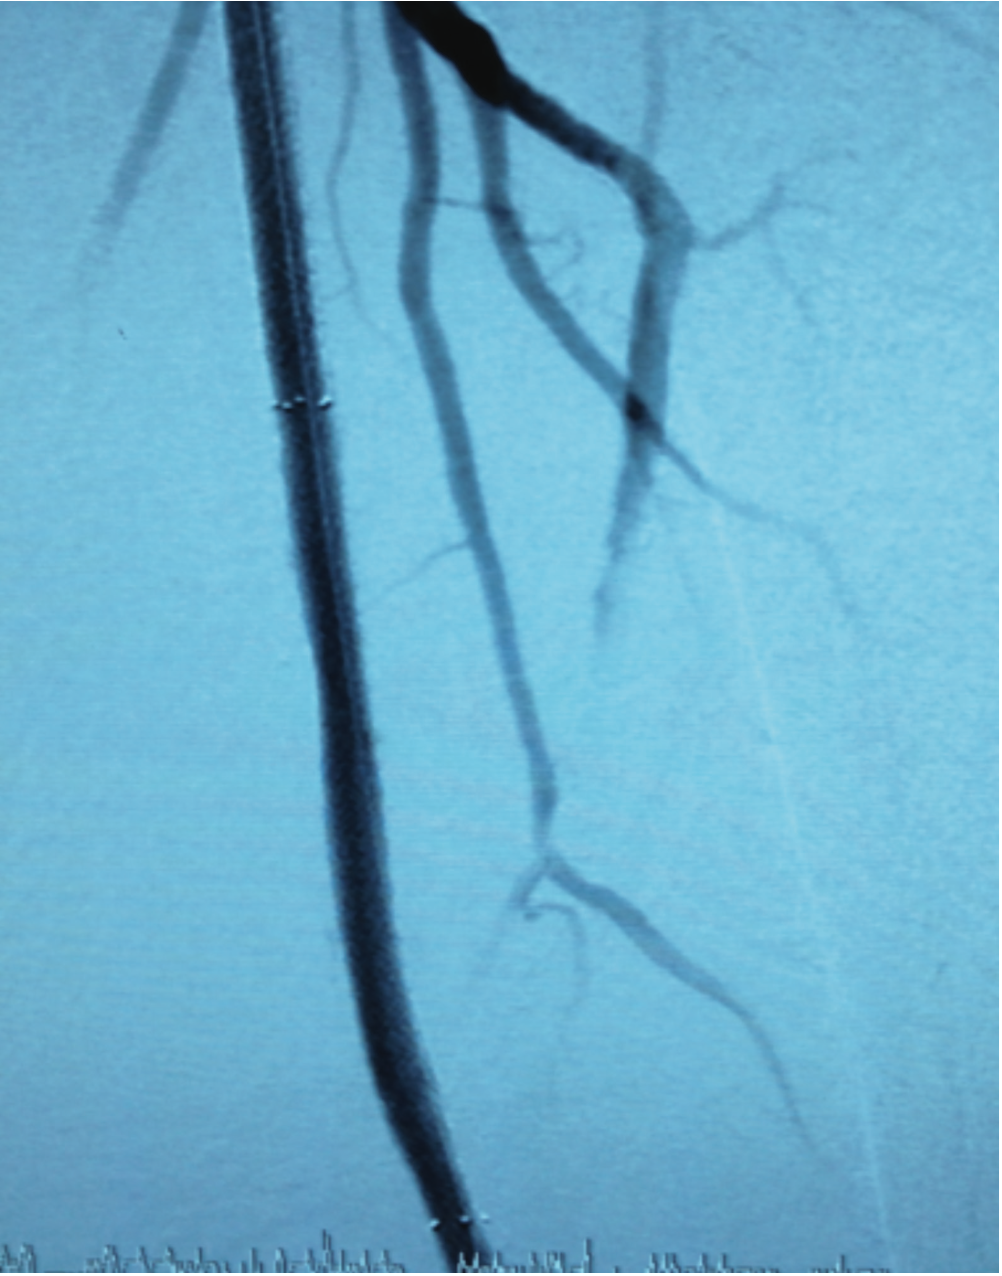

The 5 Fr system was exchanged for a 7 Fr 0.038-inch x 90 cm Flexor Check-Flo Raabe sheath (Cook Medical). Angiography confirmed flush occluded left SFA at its ostium (note arrow in Figure 1). We advanced a 0.035-inch x 260 cm Advantage glidewire with a 5 Fr angled-tip Glide catheter support and crossed half way down the occluded SFA. At this point, we were subintimal and could not advance any further (note upper arrow in Figure 2).

While maintaining the Runthrough NS wire in position, we advanced a 0.014-inch x 300 cm Spartacore guide wire (Abbott Vascular) from the right CFA with a Quick-Cross support catheter. We carefully navigated the wire through the entire length of the SFA into the left popliteal artery and distally into the left anterior tibial artery. At this point, we deployed four self-expanding 6 mm FlexStents (Cordis) in an overlapping fashion, measuring 380 mm in length, extending from the left distal SFA all the way up to the left SFA ostium at the level of the CFA (Figure 6). We performed final balloon angioplasty to expand the stent struts with a 5 mm x 220 mm Savvy balloon (Cordis). Final angiography showed excellent results with good distal flow (Figure 7).